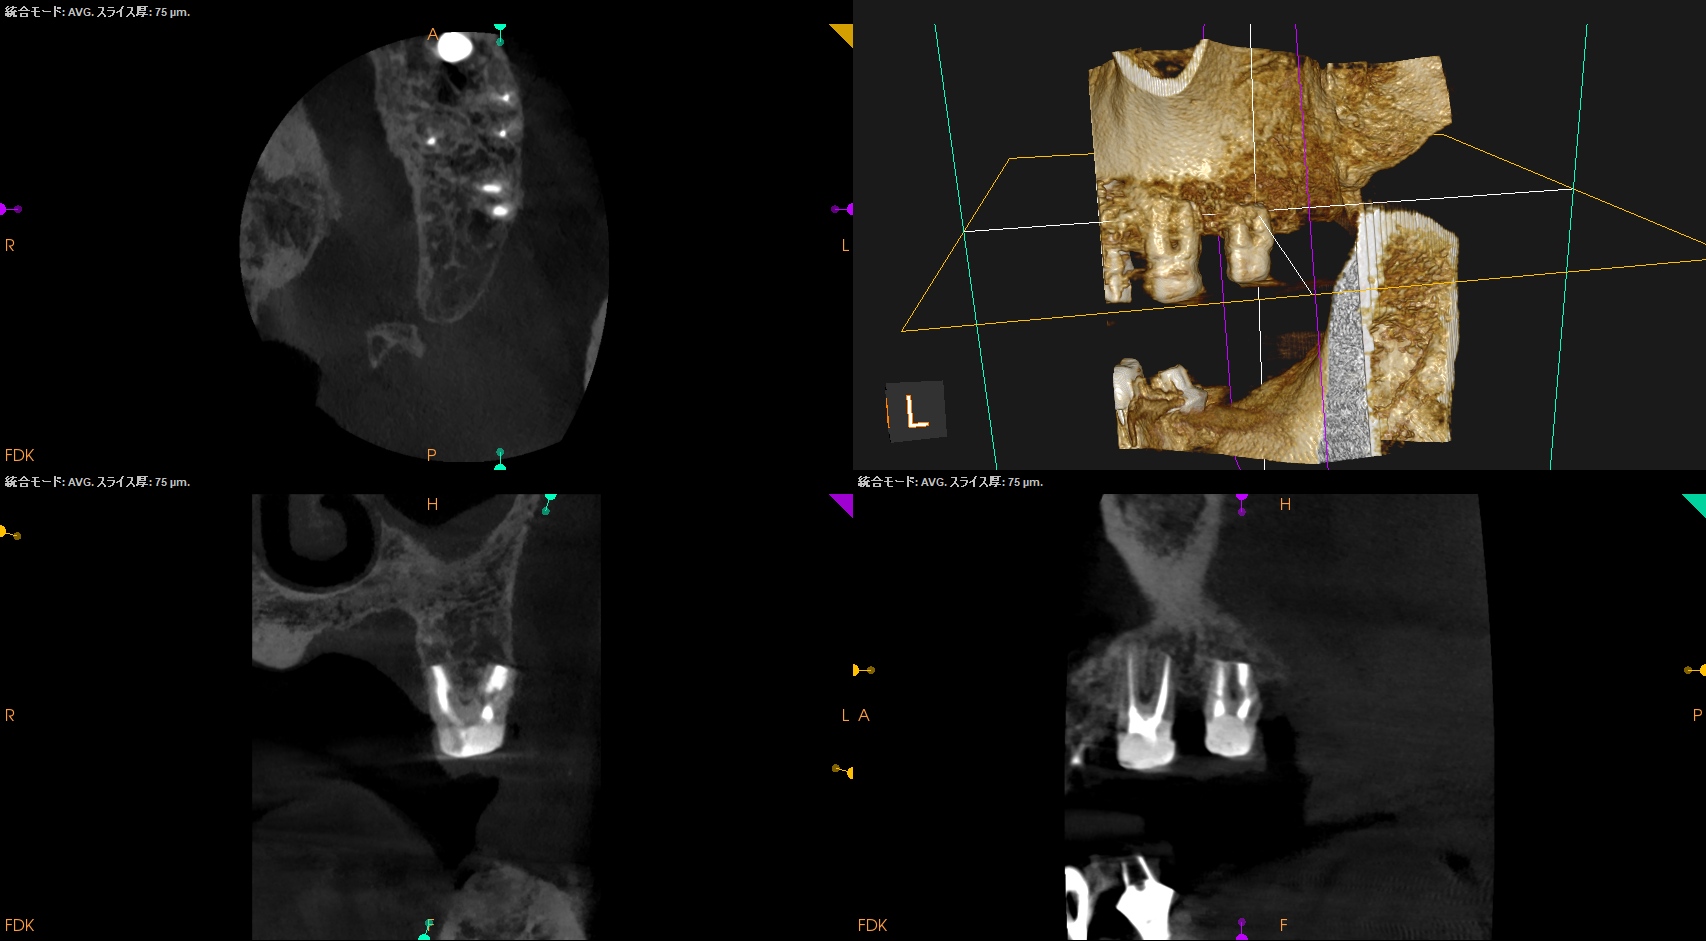

#15 Intentional Replantation 6M recall(2025.10.8)

治療直後と比較した。

歯槽骨の改善が大幅にみられた。

次回はさらに半年の1yr recallである。